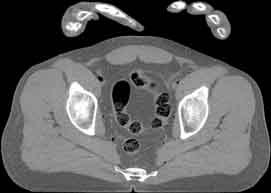

Visible Human male: Sectio transversalis 1849

CT

NMR

Pd                          / T2 \                         T1